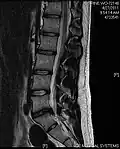

- Magnetic resonance imaging is the gold standard study for confirming a suspected LDH. With a diagnostic accuracy of 97%, it is the most sensitive study to visualize a herniated disc due to its significant ability in soft tissue visualization. MRI also has higher inter-observer reliability than other imaging modalities. It suggests disc herniation when it shows an increased T2-weighted signal at the posterior 10% of the disc. Degenerative disc diseases have shown a correlation with Modic type 1 changes. When evaluating for postoperative lumbar radiculopathies, the recommendation is that the MRI is performed with contrast unless otherwise contraindicated. MRI is more effective than CT in distinguishing inflammatory, malignant, or inflammatory etiologies of LDH. It is indicated relatively early in the course of evaluation (<8 weeks) when the patient presents with relative indications like significant pain, neurological motor deficits, and cauda equina syndrome. Diffusion tensor imaging is a type of MRI sequence used for detecting microstructural changes in the nerve root. It may be beneficial in understanding the changes that occur after herniated lumbar disc compresses a nerve root, and might help in differentiating the patients that need surgical intervention. In patients with a high suspicion of radiculopathy due to lumbar disc herniation, yet the MRI is equivocal or negative, nerve conduction studies are indicated.[44] T2-weighted images allow for clear visualization of protruded disc material in the spinal canal.

-

MRI scan of cervical disc herniation between C5 and C6 vertebrae -

MRI scan of cervical disc herniation between C6 and C7 vertebrae -

MRI scan of large herniation (on the right) of the disc between L4 and L5 vertebrae -

A rather severe herniation of the L4–L5 disc -

Example of a herniated disc at L5–S1 in the lumbar spine